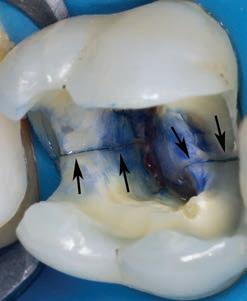

Figure 6. (a) Periapical radiograph showing failure of a revascularization procedure after 6 months on the maxillary left central incisor of a 9 year old patient; (b) photo captured during a surgical procedure that was used to communicate the poor prognosis of a vertical root fracture (black arrows) of the immature root and that the tooth will have to be extracted (c) image of extracted tooth after the fracture line (blue arrows) was stained with methylene blue dye

• Identification of structural dentine cracks (Fig.7)

Figure 7. Maxillary left first molar of a 54 year old male patient that presented with irreversible pulpitis. After removal of the previous restoration, two structural dentine cracks (black arrows) were noted and stained with methylene blue to follow the extent and depth into the pulp chamber